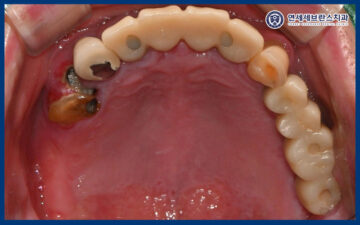

25.06.21 / 25.07.19

이렇게 임플란트의 치유기간을 거쳐

잇몸뼈와 잘 결합되어

최종 보철 작업을 시작하였습니다.

먼저 정밀한 보철물 제작을 위해

인상 채득을 진행하였으며,

이를 바탕으로 맞춤형 지대주를

제작하였습니다.

곡반정동치과 곡반정동치과 곡반정동치과

곡반정동치과 곡반정동치과

25.07.19

그리고 맞춤형 지대주에 맞는

최종 보철을 제작하여

맞춰보았습니다.

보철물의 형태와 색상,

교합 상태를 꼼꼼하게 확인한 뒤

불편한 부분은 없는지 점검하며

세밀한 조정을 시행하였습니다.